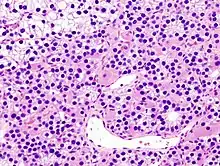

- Третинний. Вторинний гіперпаратиреоз при хронічниму гемодіалізі швидко переходить в третинний гіперпаратиреоз, коли гіперплазія паращитовидних залоз трансформується в аденому, надмірно секретуючий паратгормон.

- Аденома паращитоподібної залози